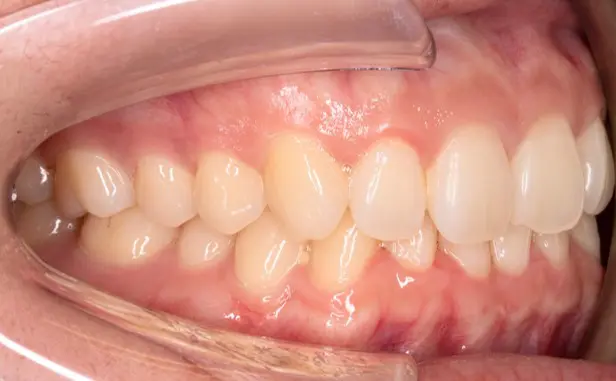

Before

After